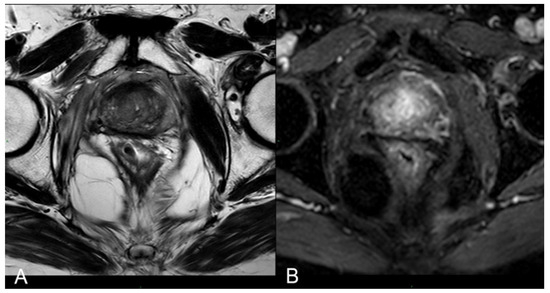

3.2. mpMRI-Derived Results